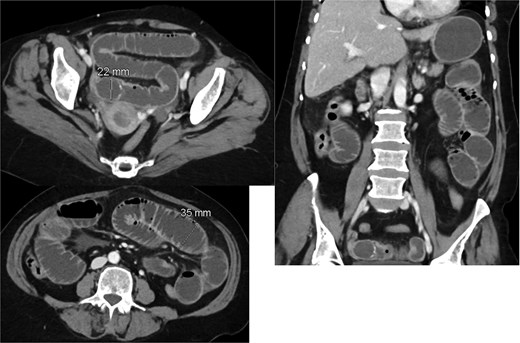

Given the absence of a stone in the ileum, we continued with conservative management. A repeat CT scan was performed 2 days later (Fig. 2). The new imaging demonstrated that the gallstone had passed through the ileum and had reached the mid descending colon. As the stone had migrated to the colon, and the CT showing picture of paralytic ileus, the decision was made to continue with conservative management, including monitoring the patient’s symptoms and providing supportive care.

Interval passage of the previously small bowel obstructing gallstone seen now at the mid descending colon with proximal colonic distention however no signs of mechanical bowel obstruction. The small bowel loop is dilated and fluid-filled without definite transition zone; there is associated mild small bowel thickening, findings are likely representing postoperative changes.